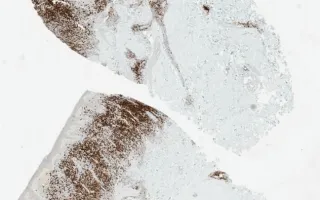

Skin, Mycosis fungoides, CD20 stain

Immunohistochemical studies for MF include: CD3, CD20, CD4, CD8, CD2, CD5, CD7, CD30, CD56, and Ki-67. Since MF is a T cell lymphoma, the atypical lymphocytes are CD3+ and CD20-. The majority of MF cases have CD4+ neoplastic T-cells, however approximately 20% of cases can be CD8+. Loss of one pan T cell marker such as CD7 and CD5 is common. MF is CD30- and CD56- (cutaneous anaplastic large-cell lymphoma is CD30+) although there have been cases of transformed MF which were CD30+.

This slide shows CD20.